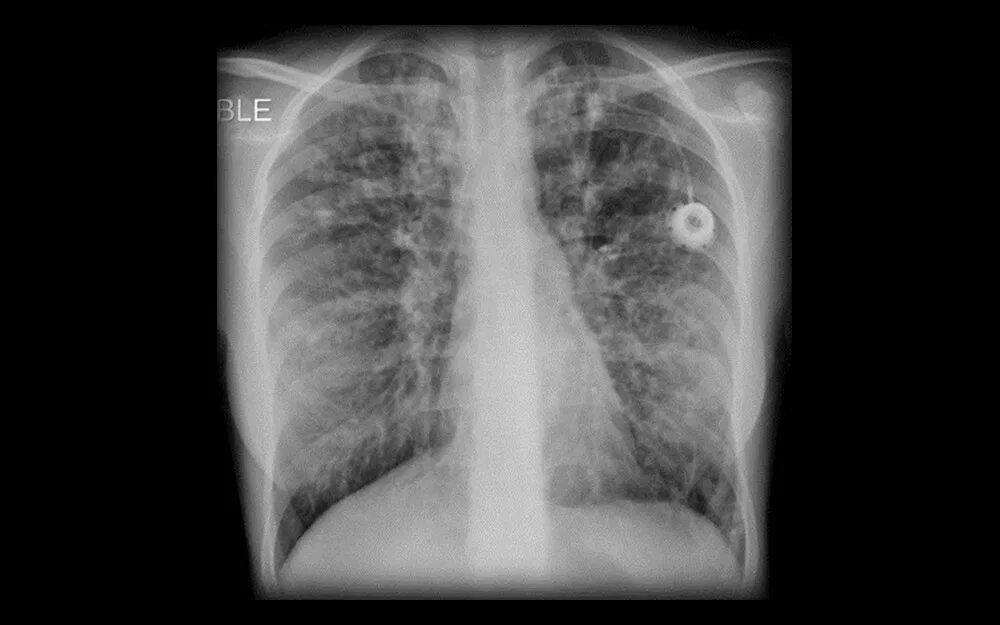

Пневмофиброзные изменения